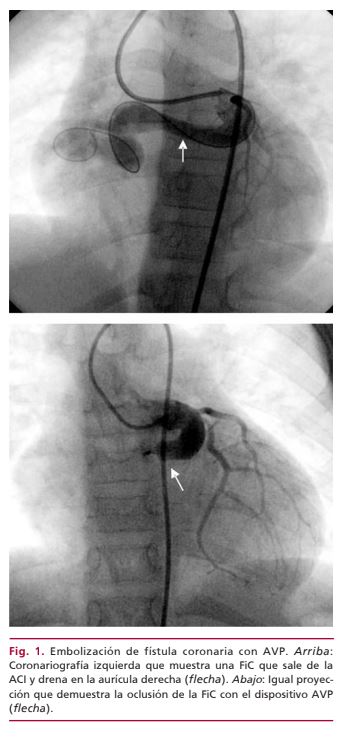

La fístula coronaria congénita es una patología poco frecuente y en general asintomática, por lo que muchas veces se diagnostica por un hallazgo incidental. Con dependencia de la repercusión hemodinámica, algunos siguen una conducta conservadora, otros indican tratamiento quirúrgico o, más recientemente, oclusión por cateterismo. Se presenta el caso de una paciente con una gran fístula coronaria-cameral, que se trató mediante embolización percutánea con dispositivo Amplatzer vascular plug. No se presentaron complicaciones durante el procedimiento ni en el seguimiento.